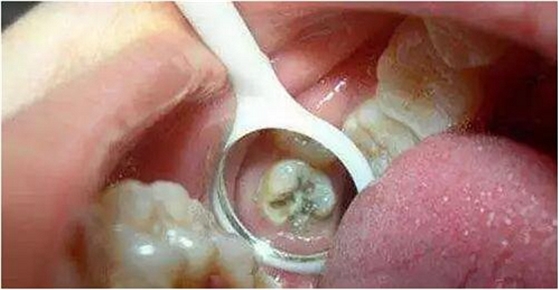

*牙髓炎:深齲由于齲洞離牙髓比較近,齲洞內(nèi)的細(xì)菌和細(xì)菌所產(chǎn)生的毒素容易滲透到牙髓組織,引起牙髓炎,使患牙發(fā)生劇烈疼痛。這個(gè)階段,根管治療是唯一可行的辦法。治療時(shí)需要麻醉后將牙髓組織清除,即大家所說的“殺神經(jīng)”。

*根尖炎:牙髓炎得不到及時(shí)治療,或治療不徹底,細(xì)菌可通過牙髓向根尖擴(kuò)散,引起牙齒根尖部的病變,如根尖炎、根尖周炎、根尖膿腫等不同疾病。根尖部的病變急性發(fā)作時(shí)也會(huì)引起較重的疼痛,甚至牙齦及面部腫脹。根尖炎也需要行根管治療。